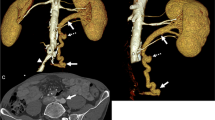

The arising direction of the initial segment of the RRA was measured in axial images, with a horizontal and a perpendicular straight line made through the center of the aorta where the RRA originated. Hour hand positions of 9–12 o’clock were projected and fused with the lined images, and the RRA arising directions were recorded as the hour hand positions (Fig. 1c, 2b).

CT imaging showed a notable RRA-sourced LRV compression in a 48-year-old male with isolated iliac dissection (arrows in a). The initial segment of RRA (green arrows in b, c, and e), arising from an 11 o’clock direction (b), transversed behind and compressed (white arrowheads in b, c, and e) the ending segment of the LRV, where it joins the IVC. A dilated adrenal vein (the axes’ intersection in d) was visualized and measured. SMA, superior mesenteric artery; short-shafted white arrows (without text), LRV; other legends are the same as in Fig. 1

The most common RRA arising orientation of the 44 patients were 10:00 and 10:30 (Table 1; Fig. 1c), with 17 (38.64%) and 12 (27.27%) cases, respectively, and with 3 (6.82%), 6 (13.64%) and 6 (13.64%) cases at 9 o’clock, 9:30, and 11 o’clock (Fig. 2b), respectively. There was no noticeable orientation difference between the groups and subgroups. Accessory right renal arteries were seen in 5 cases (4 Renal and 1 Non-renal), compressing the end of the LRV in 1 Renal patient.

Polguj reported an 11 o’clock direction of proximal RRA, which compressed the LRV in a Caucasian female hospitalized due to choledocholithiasis [10]. In selected subjects, we found 8.9% (5/44) of patients have such an RRA arising direction (Fig. 2b). Notably, 68.2% (30/44) of the total cases had an arising direction of 10 o’clock or 10:30. In contrast, the proportion of those with a 9 o’clock arising direction accounts for only 6.82% (3/44). Though no corresponding significance between the Compressed and the Non-compressed subgroups was witnessed, a possible meaning of this finding is that the high proportion of the forward RRA course of its starting part might lay the ground for the direct contact with LRV and further compression of it by the RRA.